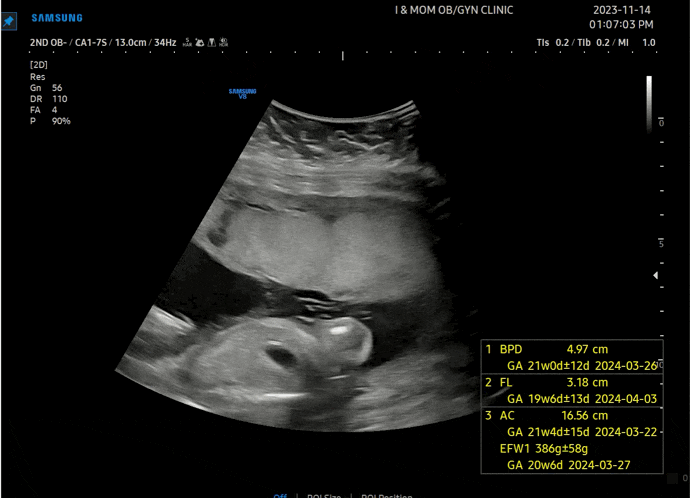

쌍둥이 임신 20주 초음파 배크기 임산부 잠옷 임부복 추천

#임신20주차 11/14(화) 강릉 아이앤맘 4주만에 방문 생각보다 4주가 빨리 지나갔다. 그리고 4주간 자궁 크...